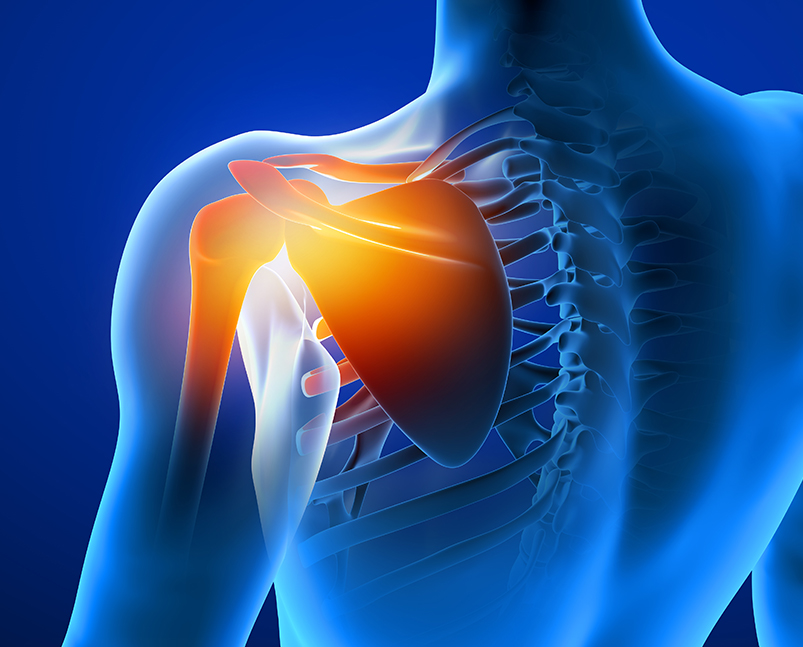

Shoulder Impingement Syndrome

Shoulder impingement, a common condition, arises when the tendon within the shoulder begins to swell and rub painfully against the bone or tissue, resulting in pain when you raise your arm. It may arise due to various conditions such as a traumatic injury, irritation or general wear and tear of the joint.

Shoulder impingement develops from compression of the rotator cuff tendons and subacromial bursa when passing through the subacromial space.